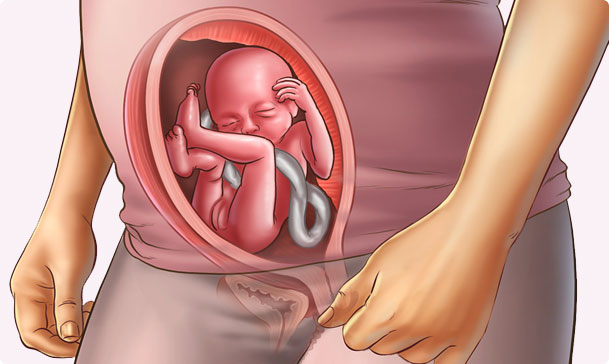

- Сформировалась и начала полноценно функционировать плацента. Теперь все, что содержится в материнской крови как через фильтр проходит через плаценту и только потом попадает к малышу. Однако стоит отметить, что некоторые вещества этот орган не способен остановить, в частности алкоголь, наркотики, никотин, некоторые лекарственные средства, токсины.

- Расположение, толщину и структуру плаценты.

- Количество околоплодных вод.

- Состояние шейки матки.

- Состояние кровообращения между маткой и плодом (эти данные получают с помощью доплера).